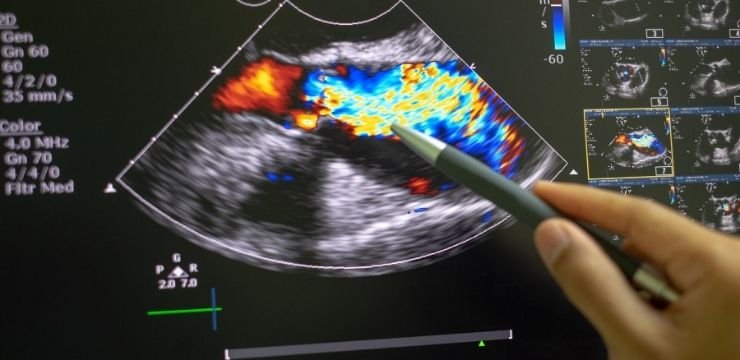

Ekokardiyografi kısa adıyla Eko ses dalgalarını kullanarak ultrasonla kalbin görüntüleme tekniğidir. Günümüzde Ekokardiyografi üfürüm nedeninin ve kalp hastalıklarının belirlenmesinde altın standart olup en önemli ve en sık kullanılan tanı yöntemidir.

Kalp bileşenlerinin yapı ve fonksiyonlarını gösteren en iyi test çoğu zaman ekokardiyografidir. Kalp boşluklarının boyutu ve kalınlığının ölçülmesi veya kalp kapakları yoluyla kalbin kanı nasıl pompalandığını ortaya koymak için ekokardiyografi kullanılır.

Ekokardiyografi kalbin yapısal anormalliklerini (VSD ve ASD gibi, kalp etrafında biriken sıvı, kalp içi kitleler vb.) tespit edebilir ve kapakların şekli, hareketi, darlıkları veya kaçakları gösterebilir.